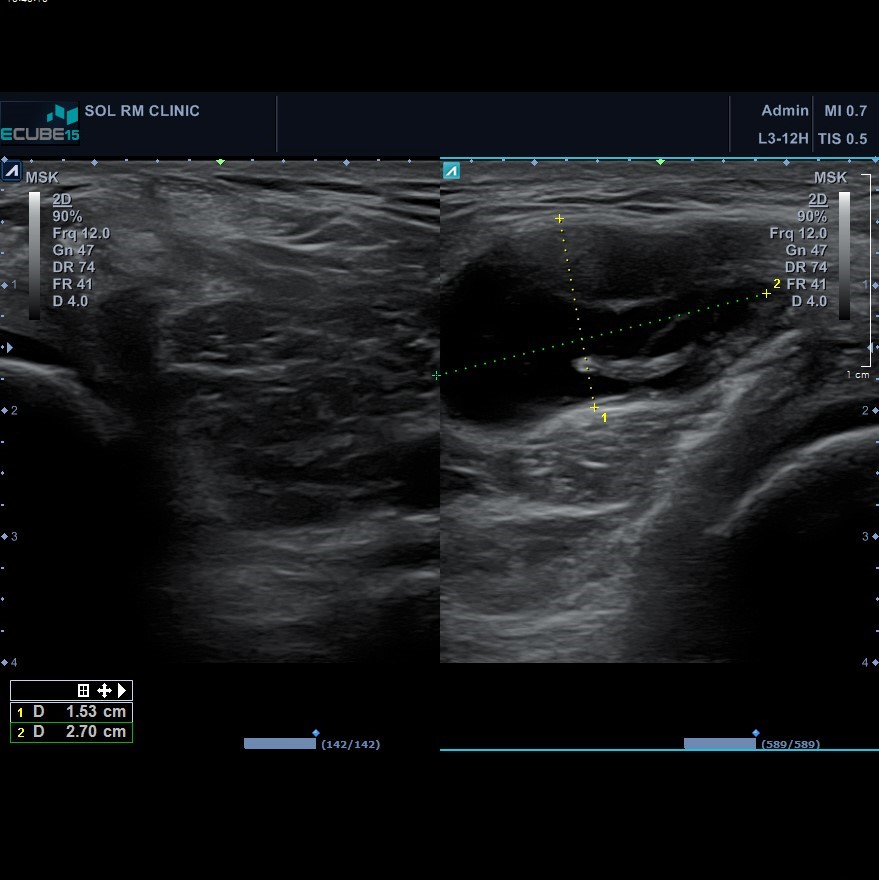

또 다른 환자분으로 39세 남자분이였으며, 큰 통증은 호소하지 않지만 10일 정도 전부터 좌측 무릎 뒤쪽에 꿀렁꿀렁한 혹이 생긴 것 같다고 호소하며 내원하신 분이 있었습니다. 진찰상 특별한 불편감, 통증, 압통도 없었으며, 오금 부위에 물렁물렁한 혹이 만져질 뿐이었습니다.

혹의 내용물을 확인하고자 무릎 초음파를 시행하혔으며, 앞서의 두 Case 보다도 더 큰 물주머니가 관찰되었으나, 혹만 만져질 뿐 다른 증상이 있지 않아 별다른 처치없이 경과관찰 하기로 하였습니다.